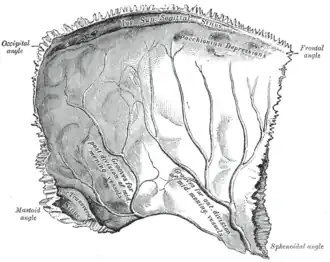

Левая теменная кость. В верхней части видны грануляции

Грануляции паутинной оболочки (лат. granulationes arachnoideae[1]) — небольшие (до 300 микрон в диаметре[2]) выпуклые образования паутинной оболочки головного мозга, выпячивающиеся через твёрдую оболочку и участвующие в циркуляции спинномозговой жидкости. Через грануляции паутинной оболочки спинномозговая жидкость выходит из подпаутинного пространства в синусы твёрдой мозговой оболочки и смешивается с основным потоком крови. Большая часть грануляций сосредоточена внутри черепа, в верхнем сагиттальном синусе, однако они встречаются во всех синусах, связанных с твёрдой мозговой оболочкой, грануляции обнаружены также в спинномозговой паутинной оболочке. На внутренней поверхности костей, образующих свод черепа, грануляции паутинной оболочки оставляют так называемые гранулярные вдавления (fovéolae granuláres), которые хорошо заметны, например, на теменной кости. Для них до сих пор используется устаревшее авторское название, пахионовы грануляции, по имени впервые описавшего их в 1705 году итальянского анатома Антонио Паккиони (1665—1726)[3].